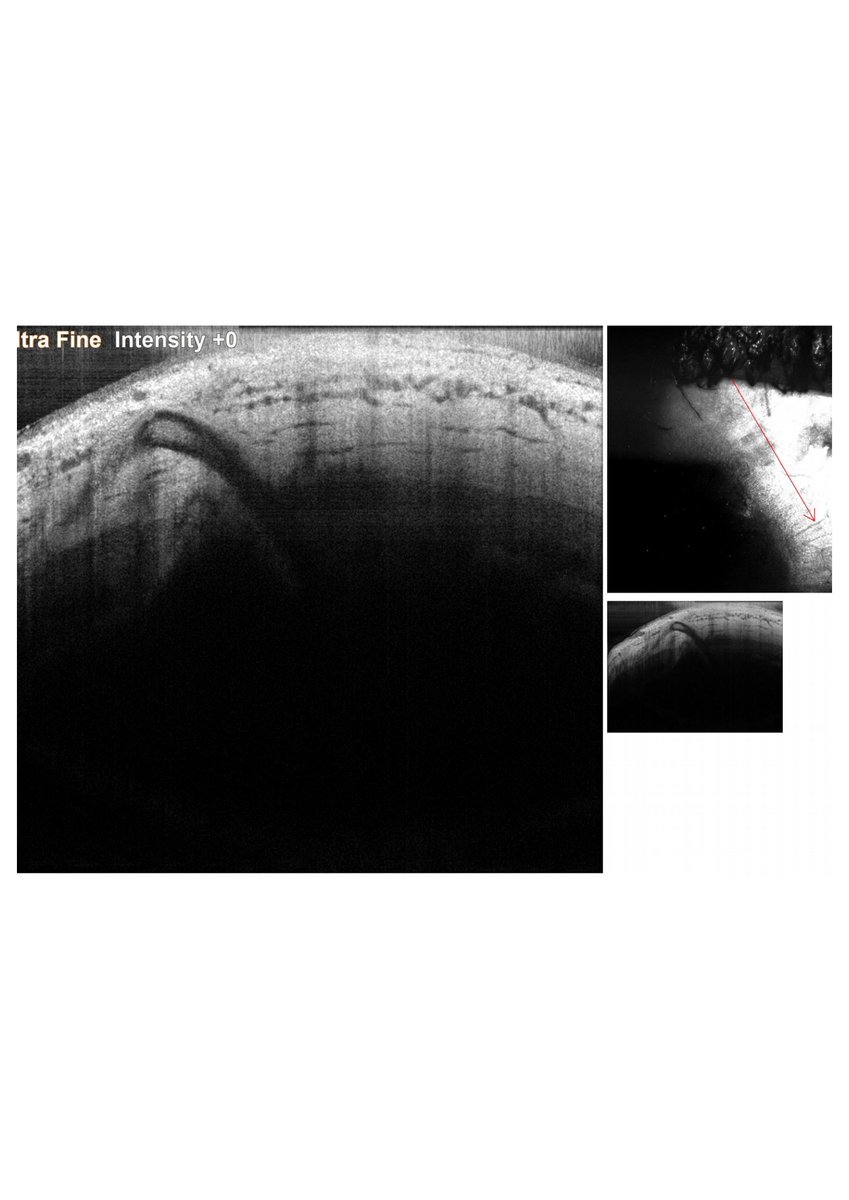

Time is Not Vision: time from open-globe injury to primary surgical repair